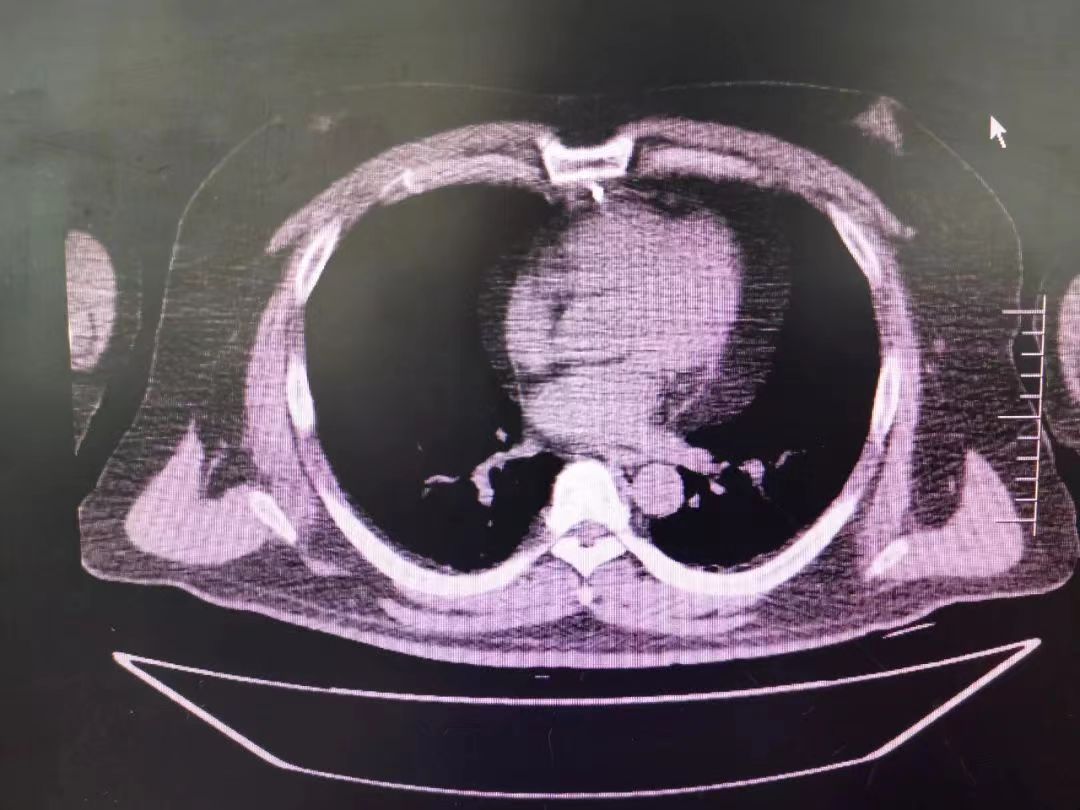

CT室門口,焦燥的家屬不停的走動著、等待著,看到醫生的到來,快速跑到醫生面前說:“醫生,快幫我看看,病人怎么樣”。陳醫生過去一看,一個體型偏胖的患者平躺在床上,一把剪刀齊根直插胸口觸目驚心,陳醫生不由眉頭一緊,轉身去看電腦CT影像 --剪刀斜著刺入胸骨,將胸骨完全穿透,刀尖距離心包約1-2mm,正下方是主動脈,大量心包積液?再一看,患者肥胖,脂肪組織多,不排除脂肪偽影。考慮患者血壓相對平穩,由于緊張導致心率快,立刻安撫患者,讓其保持安靜,盡量避免咳嗽,避免深呼吸和過多運動。隨即撥通了武小剛主任的電話:“主任,這有一位患者,銳器刺傷不排除已經損傷到心臟,病人目前血壓平穩”“嚴密監測患者病情變化,準備急診手術,我馬上到”武主任說。